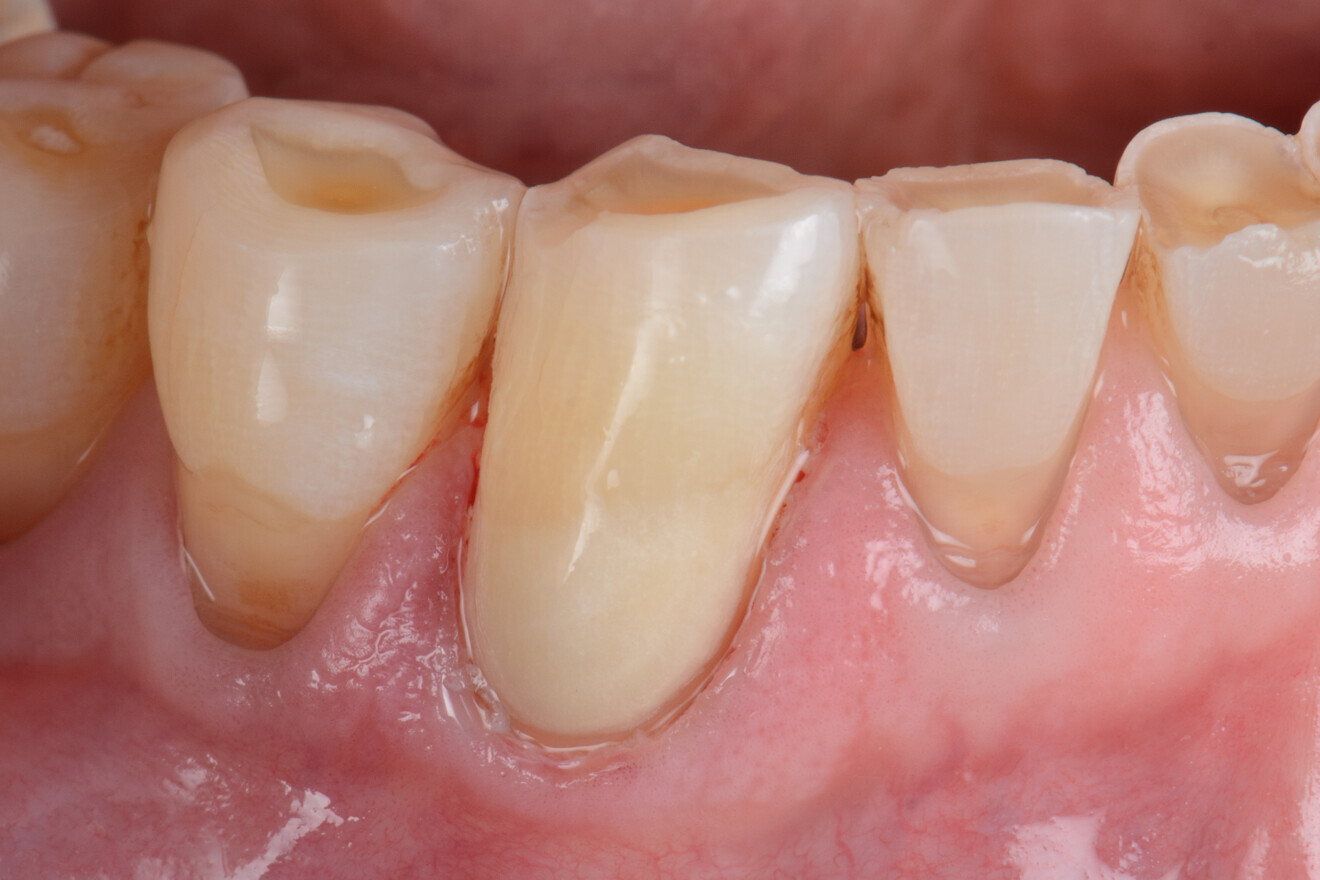

Lésion cervicale non carieuse, avant traitement. Dans les études cliniques randomisées et contrôlées, les verres hybrides montrent des résultats prometteurs pour la restauration des lésions cervicales. (Photo : Prof Falk Schwendicke)

En raison de la perte osseuse parodontale, les patients âgés présentent souvent des espaces interdentaires ouverts qui sont prédisposés aux lésions carieuses radiculaires (Fig. 1). Ces patients doivent veiller à une hygiène de ces espaces au moyen de brossettes interdentaires et d’un dentifrice fluoré.

Fig. 1 : Les racines exposées sont prédisposées au risque carieux ; elles se déminéralisent plus tôt et plus rapidement, car la dentine ou le cément n’est pas protégé par l’émail ou l’alvéole.